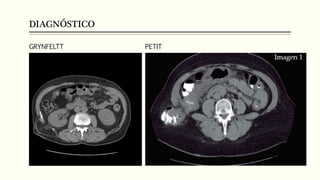

DIAGNÓSTICO

1. ECOGRAFIA 2. TOMOGRAFÍA

GRYNFELTT PETIT